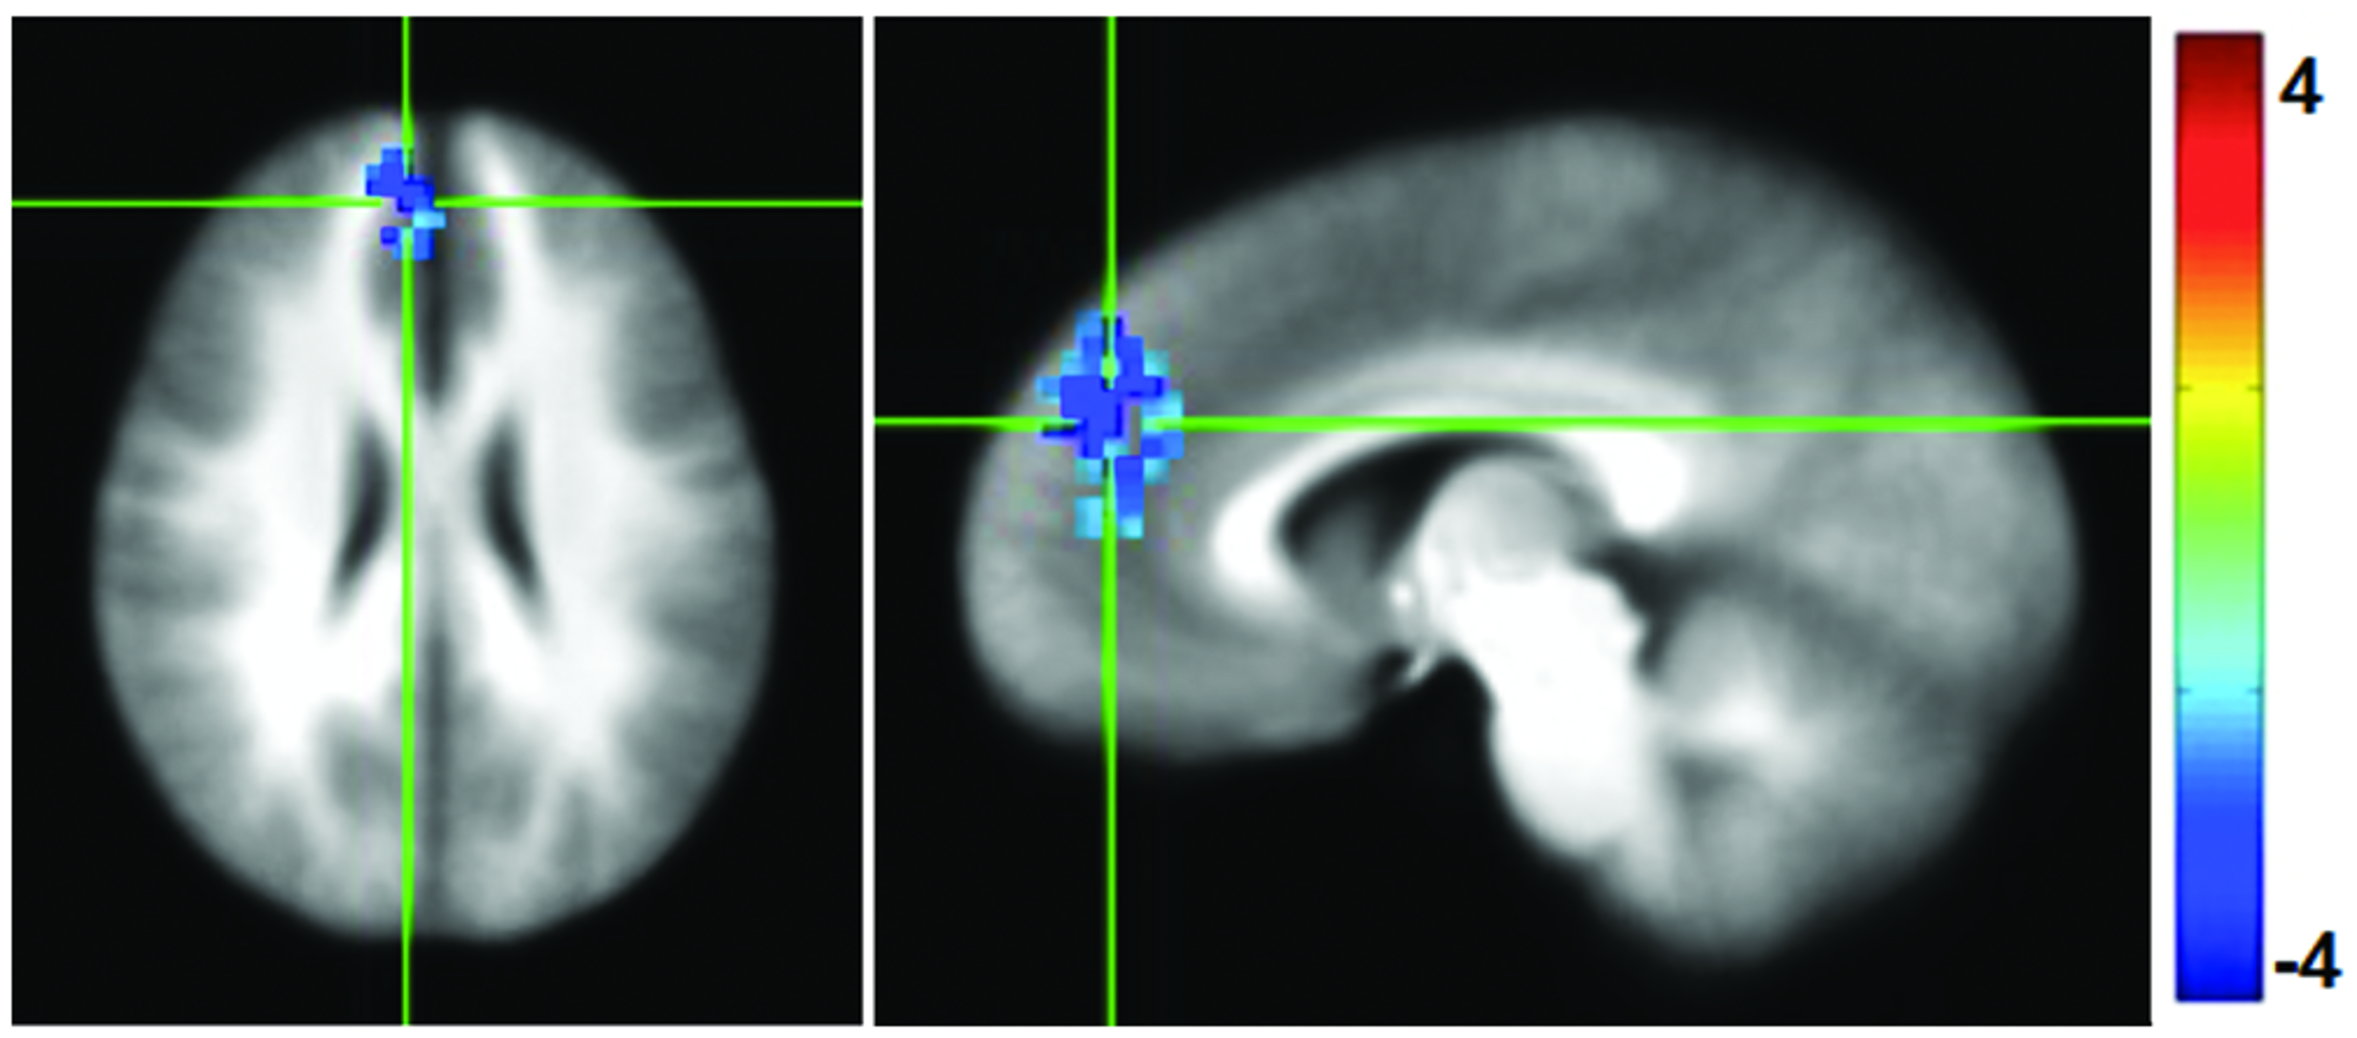

Functional connectivity maps were generated by computing the correlation coefficient between the average time series in the PCC and the rest of the brain, and then normalized to Fisher-Z values for comparison. Following the mPEAK training there was a significant decrease in the FC with the seed in PCC in one cluster (Figure 4). The region contained 152 voxels, with the center of mass at (x = -6, y = -45, z = 25), and primarily included portions of the right medial frontal gyrus, right superior frontal gyrus and right ACC. In other words, this cluster showed lower correlations with the PCC after the mPEAK training.

FIGURE 4

t-statistics for changes (Post-mPEAK Minus Pre-mPEAK) in functional connectivity with the seed in PCC (p<0.05, corrected); negative values in the figure show the decrease in functional connectivity after mPEAK training.

The resting state FC analysis was aimed to determine whether the mindfulness training would affect the resting state FC in DMN with the focus on its midline node, PCC. Following the mPEAK training we found decreased FC between PCC and right medial frontal gyrus, right superior frontal gyrus and right ACC. A similar result was found during task where meditators showed lower FC between the PCC and other cortical midline structures including the ACC and mPFC (Garrison et al., 2013). PCC activation is thought to be related to multiple aspects of cognitive processes including attention disruption, craving, and self-referential processing while its deactivation is associated with being mindful of the present moment (Brewer et al., 2013). Lower connectivity between PCC and mPFC following mindfulness training may indicate reduced self-referential processing and may facilitate shifting between the frontal control network and the default mode network (Prosperi et al., 2009).